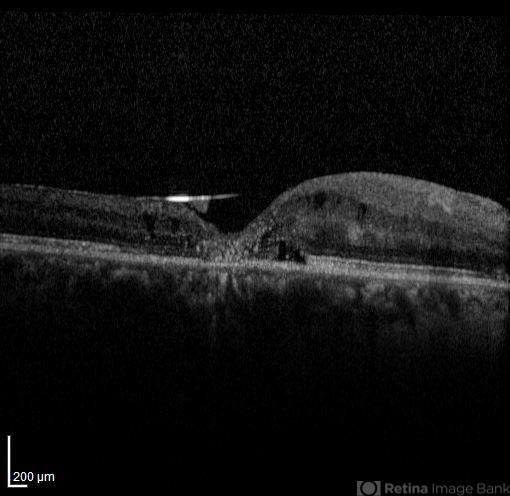

- silicone oil, optical coherence tomography (OCT)

- OCT image of the silicone oil surface bridging an enhanced foveal depression. There is the history of a rhegmatogenous retinal detachment associated with full thickness macular hole repair.